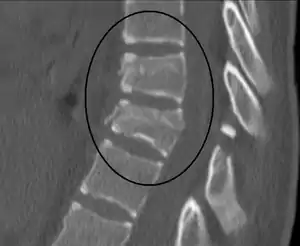

Chance fracture

| A Chance fracture of T10 and fracture of T9 due to a seatbelt during an MVC. | |